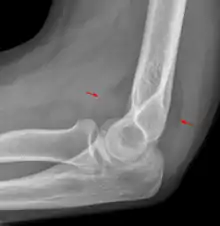

Fat pad sign: Ventral fat pad bowed and dorsal fat pad visible in a case of a nondisplaced fracture of the radius head which is not visible directly.

The fat pad sign, also known as the sail sign, is a potential finding on elbow radiography which suggests a fracture of one or more bones at the elbow. It is may indicate an occult fracture that is not directly visible. Its name derives from the fact that it has the shape of a spinnaker (sail).[1] It is caused by displacement of the fat pad around the elbow joint. Both anterior and posterior fat pad signs exist, and both can be found on the same X-ray.

In children, a posterior fat pad sign suggests a condylar fracture of the humerus. In adults it suggests a radial head fracture.

The fat pad sign is invaluable in assessing for the presence of an intra-articular fracture of the elbow. An anterior fat pad is often normal. However a posterior fat pad seen on a lateral x-ray of the elbow is always abnormal. The patient will be unable to flex their elbow and requires orthopaedic input.[2]